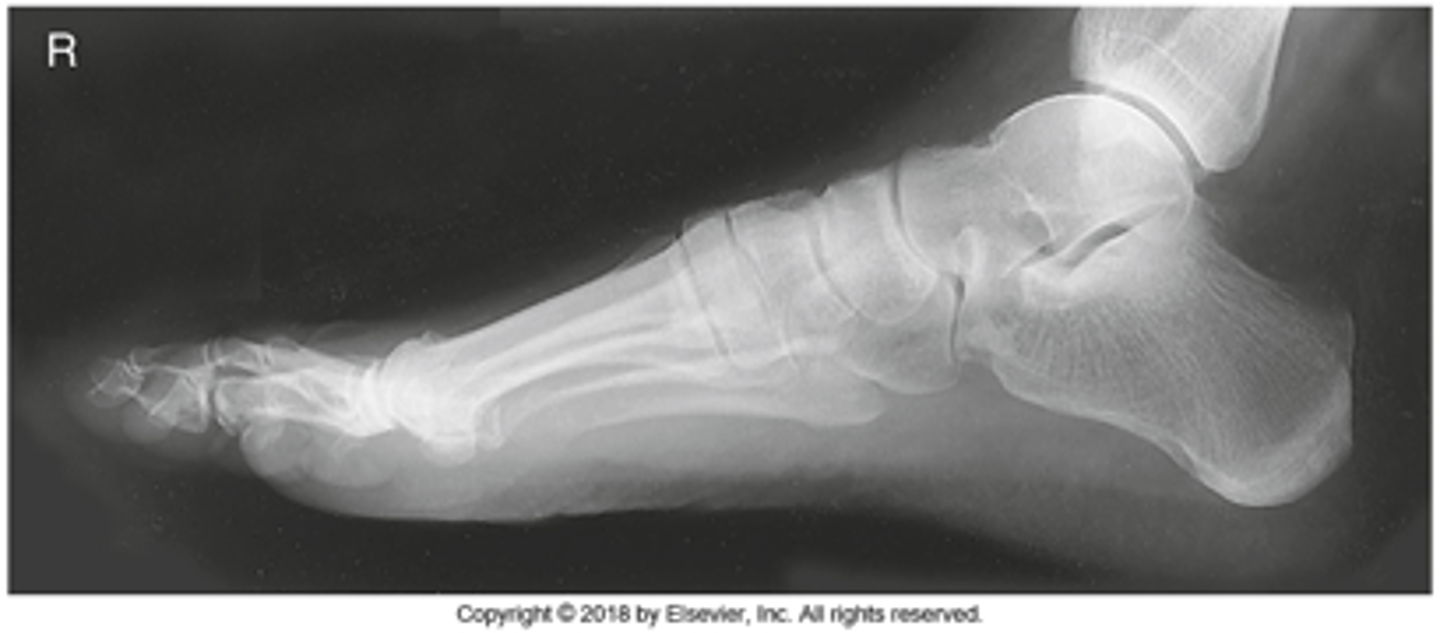

Lateromedial Foot

What projection is this?

Evaluation Criteria for Lateromedial Foot

- True lateral

- CR to midcuneiform (base of third MT)

- Entire foot visualized

- Metatarsals superimposed

- Optimal exposure factors